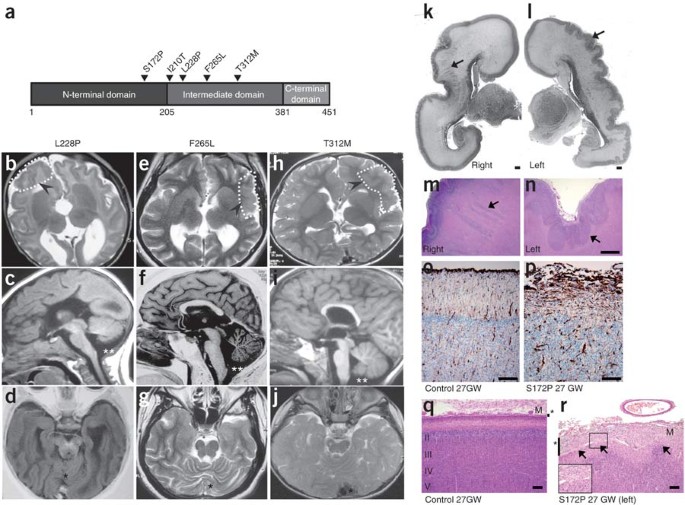

Mutations In The B Tubulin Gene Tubb2b Result In Asymmetrical Polymicrogyria Nature Genetics